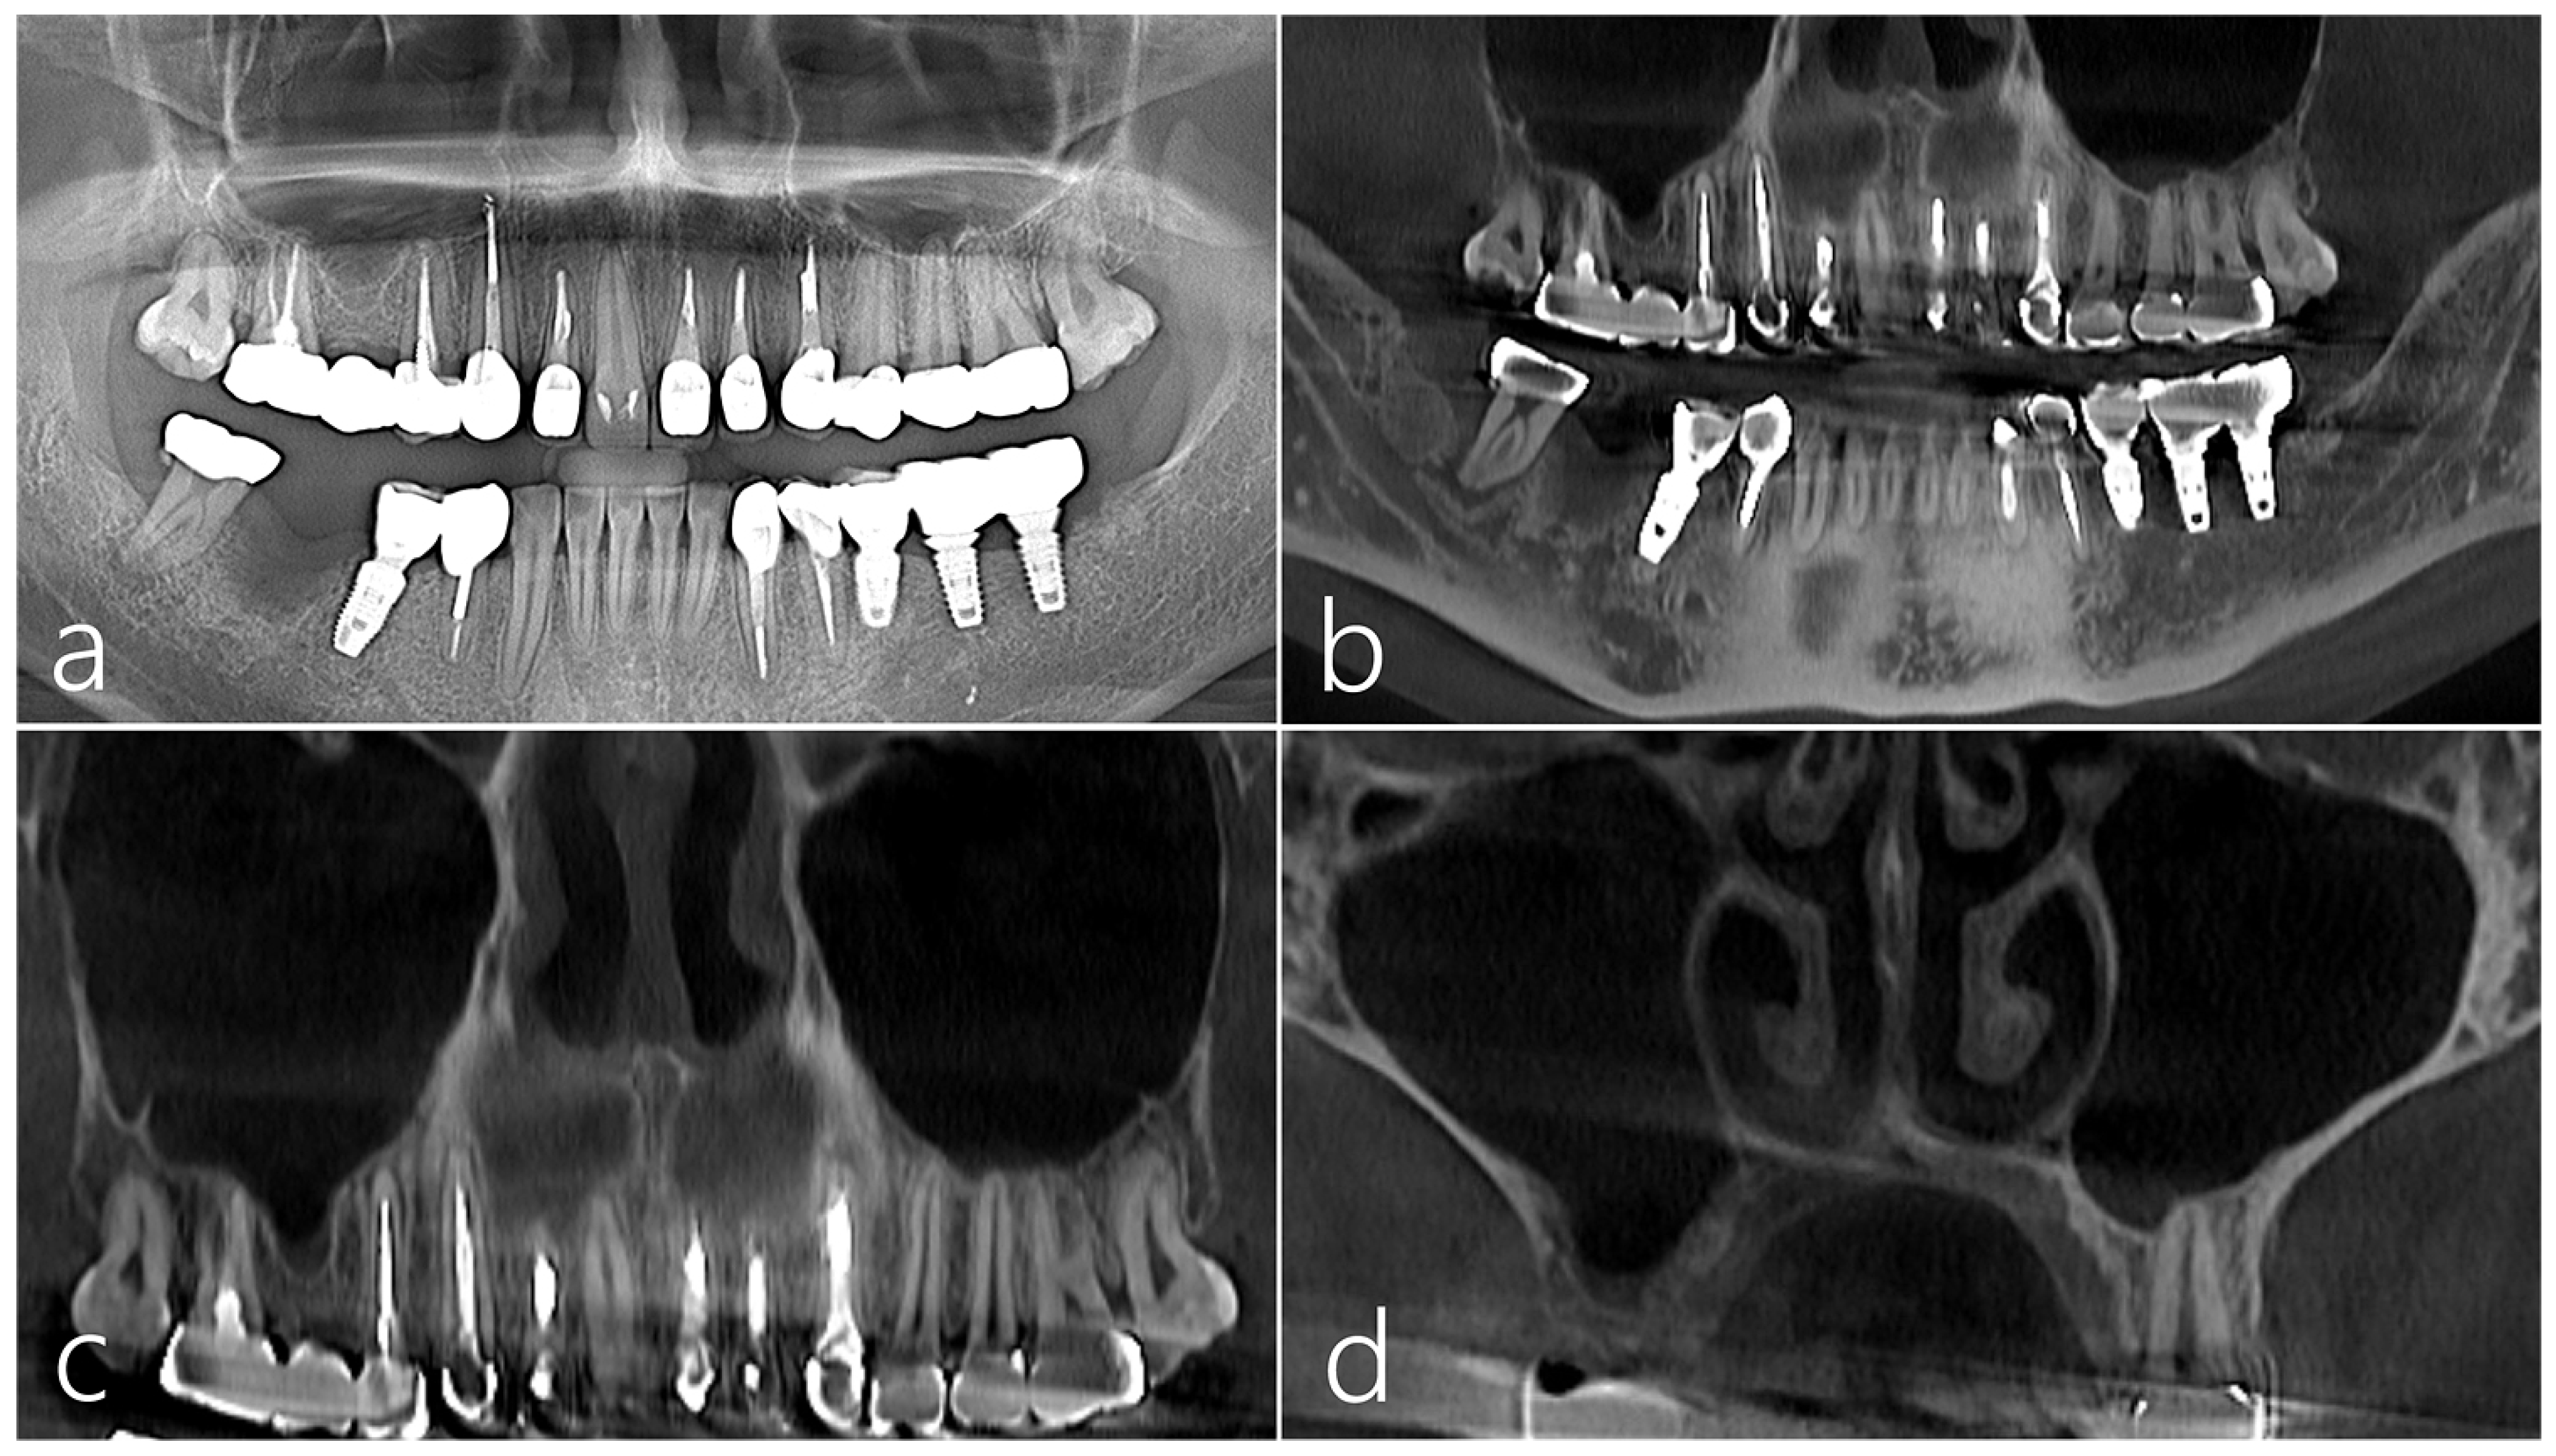

2. Case Presentation

2.1. Case 1

2.2. Case 2

2.3. Case 3

2.4. Case 4